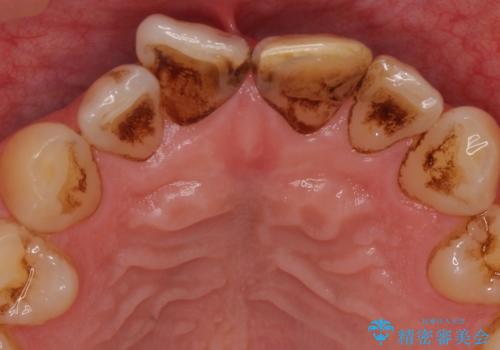

左上の前歯に詰められたプラスチック(コンポジットレジン)は、劣化し変色していました。

レジンを除去したところ二次う蝕を認めたため、丁寧に虫歯をとりました。

歯の欠損範囲が大きいことから、同様にレジン修復しても欠けやすいためセラミッククラウンによる補綴を行いました。